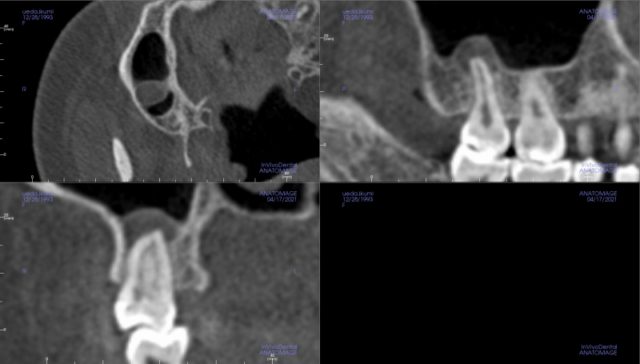

噛むと 頬骨が痛い とき 治療

慢性上顎洞炎_膿が吸引できた例_治療前

慢性上顎洞炎です。

慢性ですから、

症状は、噛むと頬骨あたりが痛い感じがする程度です。

大きな虫歯のため、

無症状で、歯の神経が死んで、

歯根の先に化膿ができた例です。

慢性上顎洞炎_膿が吸引できた例_治療後

根管治療をして、

歯は残せました。

根の先にたまった化膿が吸引され、

黒い空洞として、写っています。